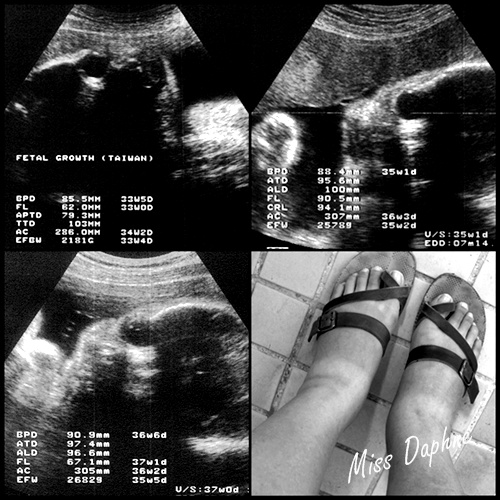

(左上:32W,右上:35W,左下:36W,右下:水腫啦!)

懷孕後期也陸續有些狀況產生:

1. 水腫:從32W開始就有了,越到晚上越明顯,被老妹笑說很像頂呱呱的呱呱包。